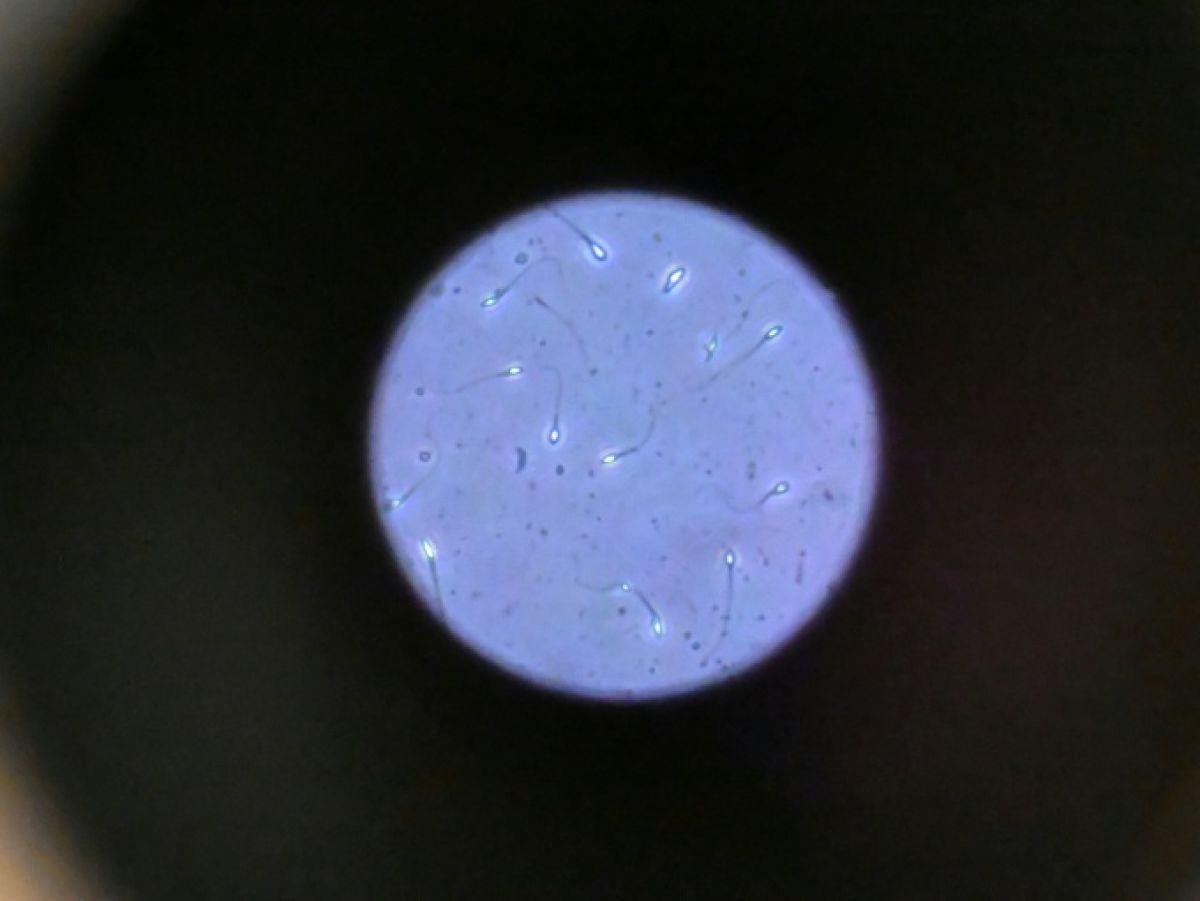

Une des difficultés réside dans le fait que le sperme n’est plus attiré vers le bas par la gravité terrestre. « Les spermatozoïdes doivent activement trouver leur chemin vers l’ovule et cette étude est la première à tester leur capacité à le faire dans des conditions semblables à ce qui se passe dans l’espace », explique à l’AFP Nicole McPherson, autrice principale de l’étude et chercheuse à l’Université d’Adelaïde (Australie).

Son équipe a utilisé une chambre en plastique imitant l’appareil génital féminin, qui leur a servi de « parcours d’obstacles miniature ». « Voyez ça comme un minuscule circuit de course… Les spermatozoïdes étaient introduits à une extrémité et devaient nager jusqu’à l’autre bout », décrit-elle.

Les chercheurs ont testé successivement du sperme de souris et humain dans ce dispositif placé dans un appareil en constante rotation pour simuler la microgravité. Les gamètes ont été environ 50 % moins performants pour naviguer à travers ce parcours que sous la gravité terrestre. Cela équivaut à une baisse de 30% du taux de fécondation réussie, selon les résultats de l’étude.